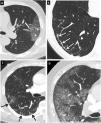

Figura 7.Hallazgos típicos de neumonía COVID-19 en tomografía computarizada (TC). Imágenes de TC de tórax con cortes de 1mm. A y B) Imágenes axial (A) y sagital (B) que muestran una lesión en el segmento posterior del lóbulo superior derecho con el signo del halo invertido (flechas). C) Extensa afectación en vidrio deslustrado con áreas de consolidación en lóbulo inferior derecho con el signo de la vacuola (puntas de flecha). D) Alteración de la arquitectura del lóbulo inferior derecho con patrón en empedrado y dilatación bronquial (flecha negra).

- •

Signo de la burbuja de aire-vacuola (fig. 7C): se refiere a un pequeño espacio hipodenso pulmonar, menor de 5mm, en el interior de la opacidad en vidrio deslustrado; podría corresponder a la dilatación patológica de un espacio fisiológico, a la sección transversal de una bronquiolectasia o ser secundario a la resolución de las consolidaciones51.

Cambios en la vía aérea, con dilataciones bronquiales (fig. 7D) en las áreas de vidrio deslustrado y engrosamiento de la pared bronquial por inflamación.

Vasos prominentes: dilatación de los vasos pulmonares peri- o intralesionales (fig. 8A) por daño de la pared capilar en respuesta a factores inflamatorios50.

Figura 8.Hallazgos típicos de neumonía COVID-19 en tomografía computarizada (TC). Imágenes axiales de TC de tórax con cortes de 1mm. A) Engrosamiento vascular (flecha) asociado a un área de opacidad en vidrio deslustrado (asterisco). B) Línea curvilínea subpleural (flecha). C) Bandas parenquimatosas subpleurales (flechas). D) Línea hipoatenuante (flechas) entre la pleural visceral y la opacidad en vidrio deslustrado (puntas de flecha).

Alteraciones pleurales y subpleurales:

- –

Engrosamiento pleural asociado a las alteraciones del parénquima pulmonar.

Línea curvilínea subpleural (fig. 8B): opacidad curvilínea fina con un grosor de 1 a 3mm, localizada paralela a la pleura y a menos de 1cm de la superficie pleural. Se relaciona con edema o fibrosis53.

Banda parenquimatosa subpleural (fig. 8C): opacidad lineal, habitualmente de 1-3mm de grosor y de hasta 5cm de longitud, localizada perpendicular a la pleura visceral, hasta la que se suele extender, que a menudo está engrosada y retraída en el punto de contacto. Refleja una fibrosis parenquimatosa y se asocia habitualmente a distorsión de la arquitectura pulmonar.

Línea hipoatenuante entre la pleura visceral y la lesión (fig. 8D).